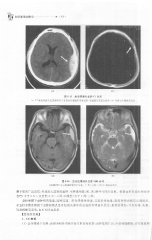

Page 312 - 医学影像诊断学